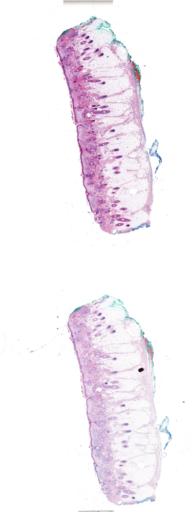

| Staining |

Hematoxylin and eosin stain method |

| Image type |

WSI_IMAGE |